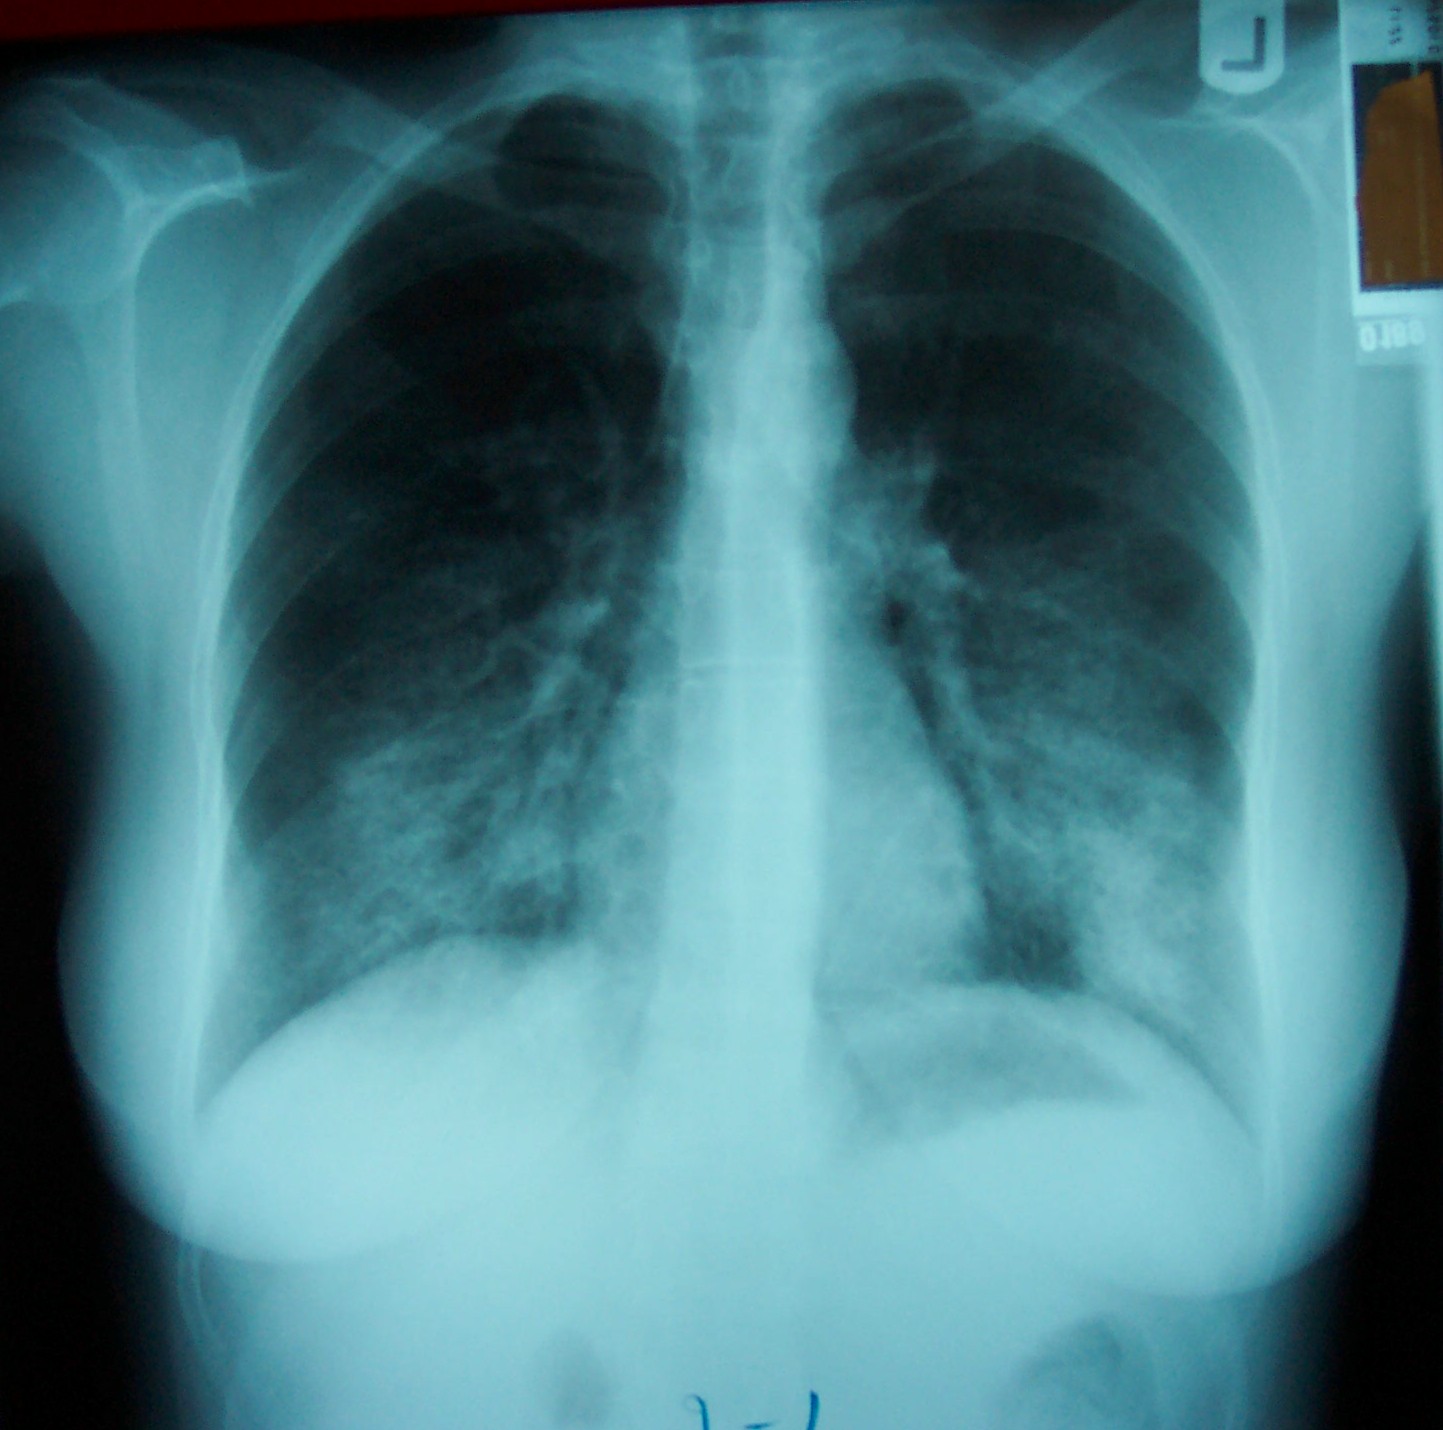

A chest radiograph showed extensive bilateral interstitial infiltrates (Figure 2).

Figure 2: Chest radiograph at initial presentation